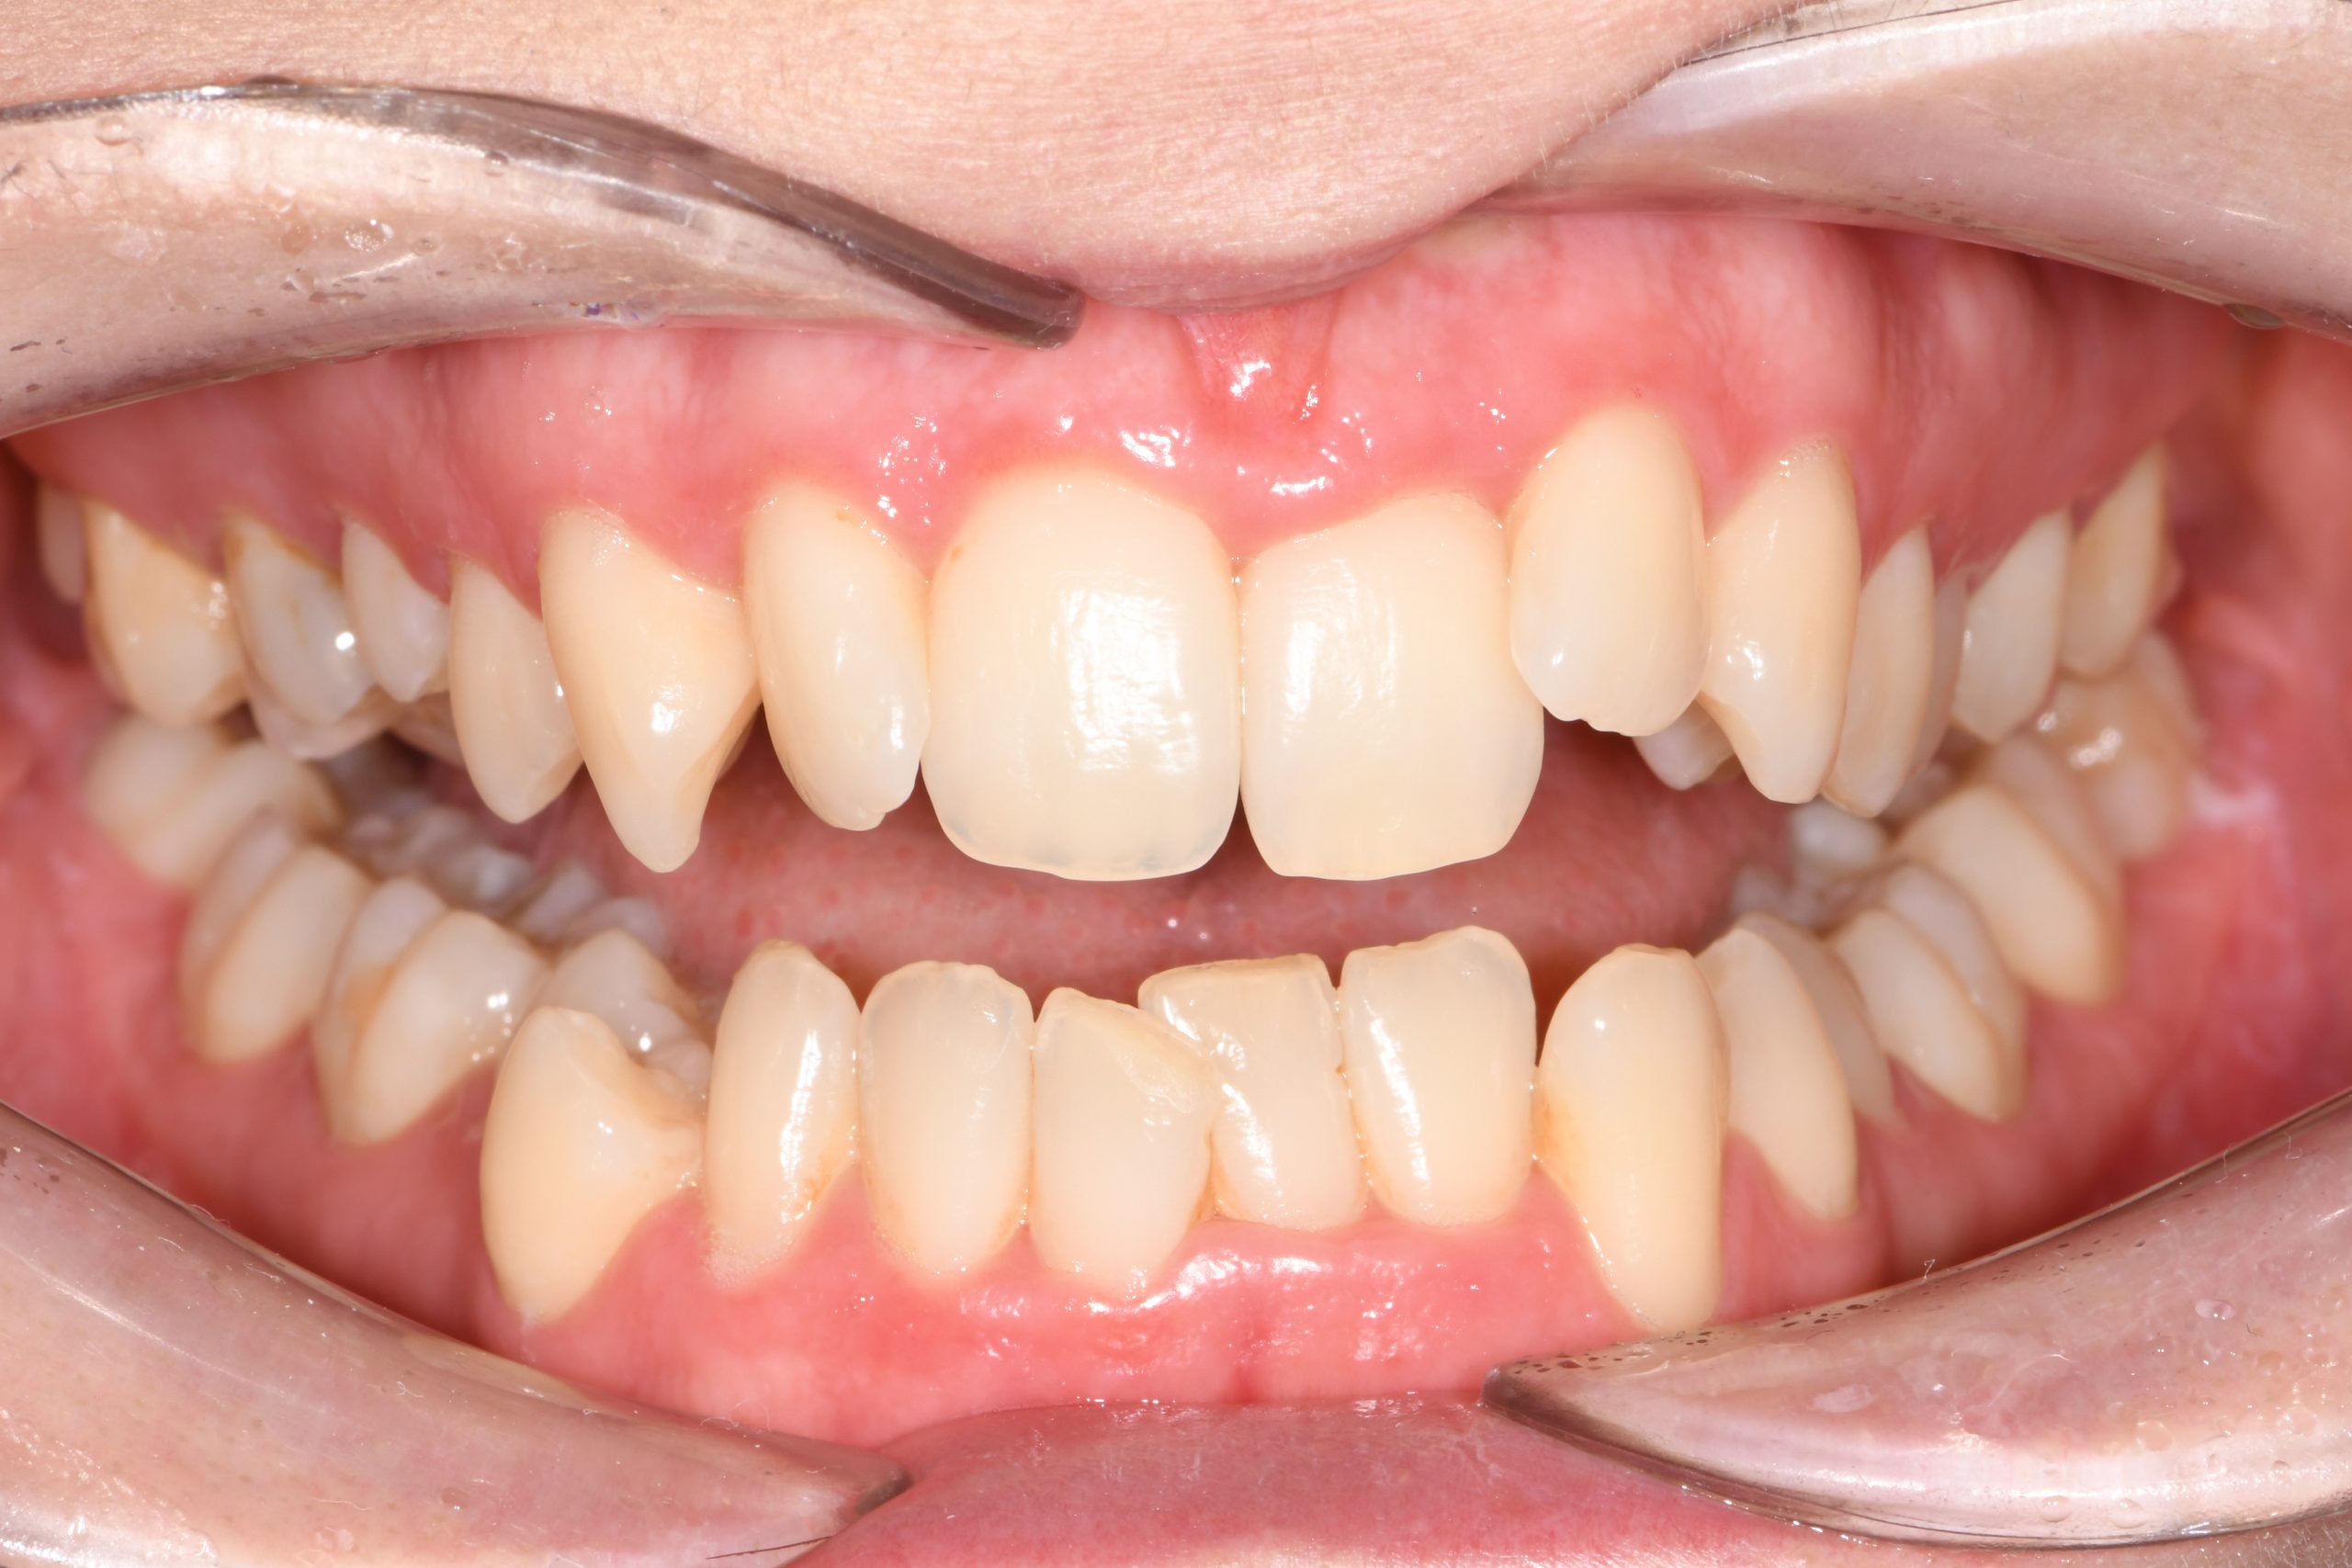

Az elmúlt évekből rengeteg szakmai referenciát tudnánk bemutatni, amelyek különböző fogszabályozási problémákat oldottak meg. Válogatva a több száz esetből, ezen az oldalon olyan képeket, információkat igyekeztünk bemutatni, amelyeknek a segítségével a jövőbeni pácienseinknek azt tudjuk üzenni: A Te fogsorod is lehet gyönyörű!

(Képeket a Pácienseink külön írásos beleegyezésével mutatjuk be!)